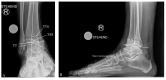

Ankle deformity is a disabling condition especially if concomitant with osteoarthritis (OA). Varus ankle OA is one of the most common ankle OA deformities. This deformity usually leads to unequal load distribution in the ankle joint and decreases joint contact surface area, leading to a progressive degenerative arthritic situation. Varus ankle OA might have multiple causative factors, which might present as a single isolated factor or encompassed together in a single patient. The etiologies can be classified as post-traumatic (e.g., after fractures and lateral ligament instability), degenerative, systemic, neuromuscular, congenital, and others. Treatment options are determined by the degree of the deformity and analyzing the pathology, which range from the conservative treatments up to surgical interventions. Surgical treatment of the varus ankle OA can be classified into two categories, joint-preserving surgery (JPS) and joint-sacrificing surgery (JSS) as total ankle arthroplasty and ankle arthrodesis. JPS is a valuable treatment option in varus ankle OA, which should not be neglected since it has showed a promising result, optimizing biomechanics and improving the survivorship of the ankle joint.